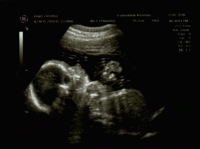

01. Juni 2010 Ultraschall https://qual.famigros.migros.ch/de.htm https://www.famigros.migros.ch/de.htm